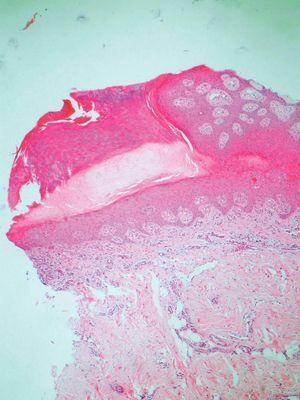

En la exploración se observó en la cara lateral externa del pie izquierdo dos placas de morfología anular de 2,5 cm de diámetro, con un centro atrófico y un borde elevado, bien delimitado e hiperqueratósico (fig. 1). Otras 10 lesiones de características similares, pero de menor tamaño, se encontraban localizadas en ambas piernas dispuestas en forma de elementos aislados (fig. 2). Se realizó una biopsia de una de las lesiones del pie izquierdo incluyendo un borde. El resultado histopatológico evidenció una invaginación de la epidermis en cuyo centro se identificaba la laminilla cornoide, en la zona subyacente a ella la capa granulosa estaba disminuida (fig. 3).

Fig. 3.--Invaginación epidérmica con la típica laminilla cornoide central, bajo la cual la capa granulosa está disminuida. (H&E, x 20.)